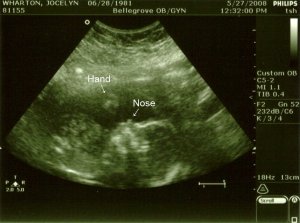

Alright, its off to bed for some much needed sleep. Even the baby is tired! Take care and we will update when there is more to tell! Lots of love from all of us!